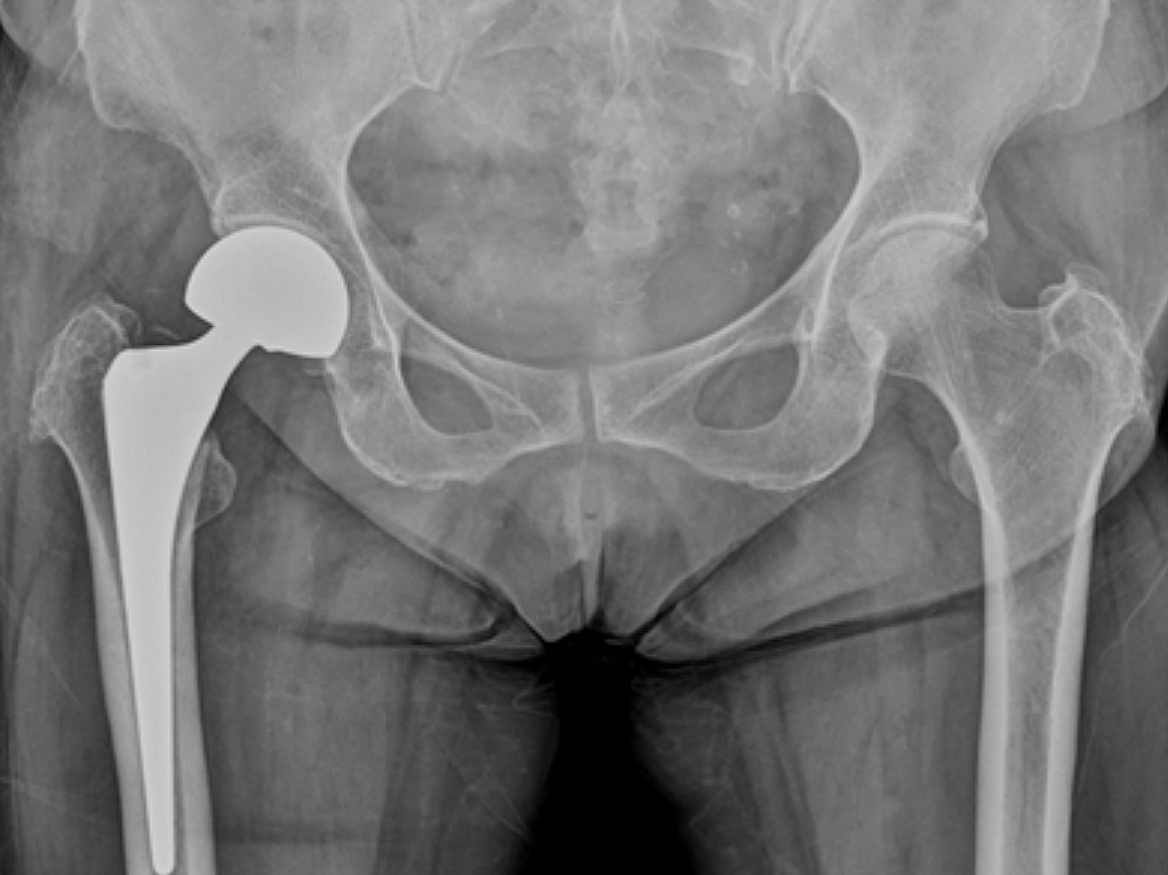

고관절 통증 증상은 조기에 발견하고 치료받는 것이 무엇보다 중요합니다. 고관절 손상이 심하지 않고 통증이 가볍다면 약물치료와 운동치료 등 보존적 치료를 통해 회복할 수 있습니다. 하지만 고관절 손상이 심하고 일상생활에 지장을 줄 만큼의 심한 고관절 통증 증상이 있는 경우라면 괴사된 관절을 제거하고 인공관절을 삽입하는 고관절의 인공관절 치환술을 해야 합니다.